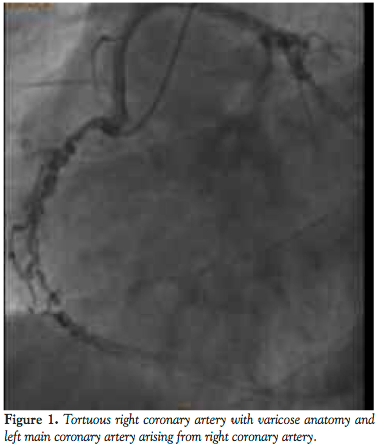

He was admitted for elective cardiac catheterization. Cineangiographic evaluation revealed a single vessel coronary artery arising from the right coronary cusp supplying the entire left system and also the right coronary artery. The right coronary artery was abnormal with significant tortuosity in the proximal and mid segments more consistent with varicose anatomy. Distally the RCA was normal. It gave rise to a posterior descending artery, which had an ostial 60% stenosis. The posterior lateral branch was a small caliber vessel and was normal. The left anterior descending artery (LAD) was a moderate caliber vessel and had no obstructive disease. The first diagonal branch divided into bifurcating branches of which the lower branch had a 70% stenosis. The circumflex artery was a very large caliber vessel that had a proximal 90%-95% stenosis. Left to right collaterals were noted.

CT angiography showed that coronary artery calcium score was 966. All vessels originated in the common origin at the right coronary cusp. The left main was long and normal as it coursed anteriorly to the pulmonary artery before bifurcating. The LAD had diffuse scattered calcifications in the proximal portion, but no critical lesions. The circumflex had diffuse severe calcifications proximally. There was a proximal 90% stenosis, which was mixed plaque. The RCA was dominant. The midportion of the vessel had a corkscrew configuration. Proximal to this was 50% stenosis of soft plaque.